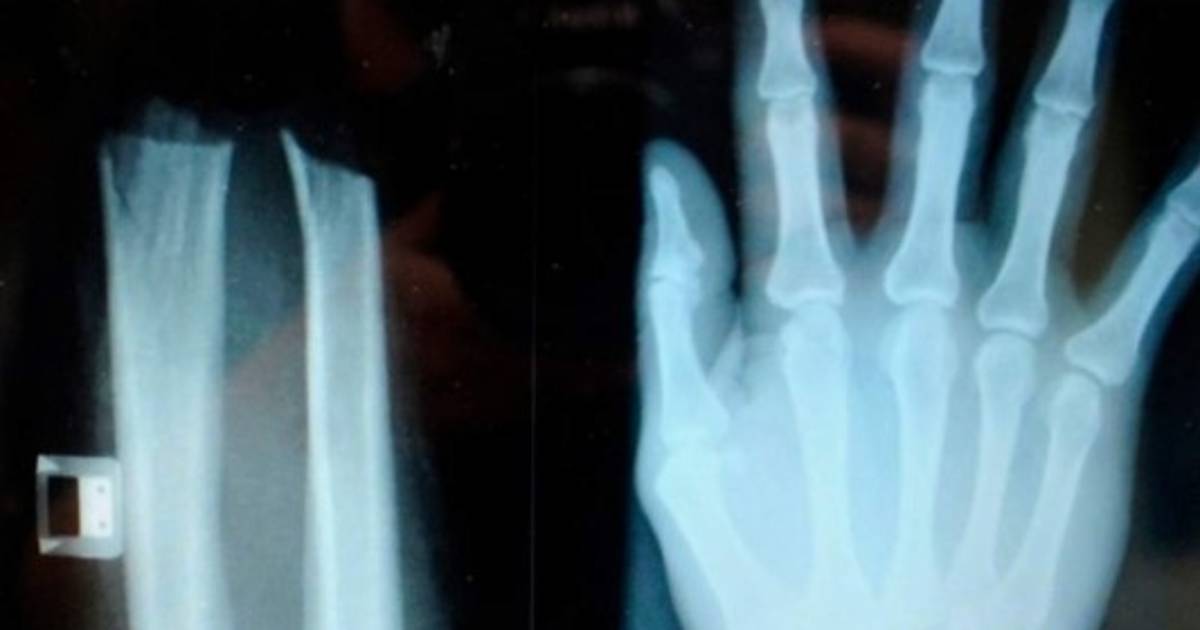

'Junto a un cómplice, se amputó deliberadamente la mano a nivel de la muñeca con una sierra circular con la esperanza de hacer creer que era un accidente', dijo un portavoz de la policía de Liubliana, Valter Zrinski.

La mano pudo ser recosida de urgencia en el hospital universitario de la ciudad.